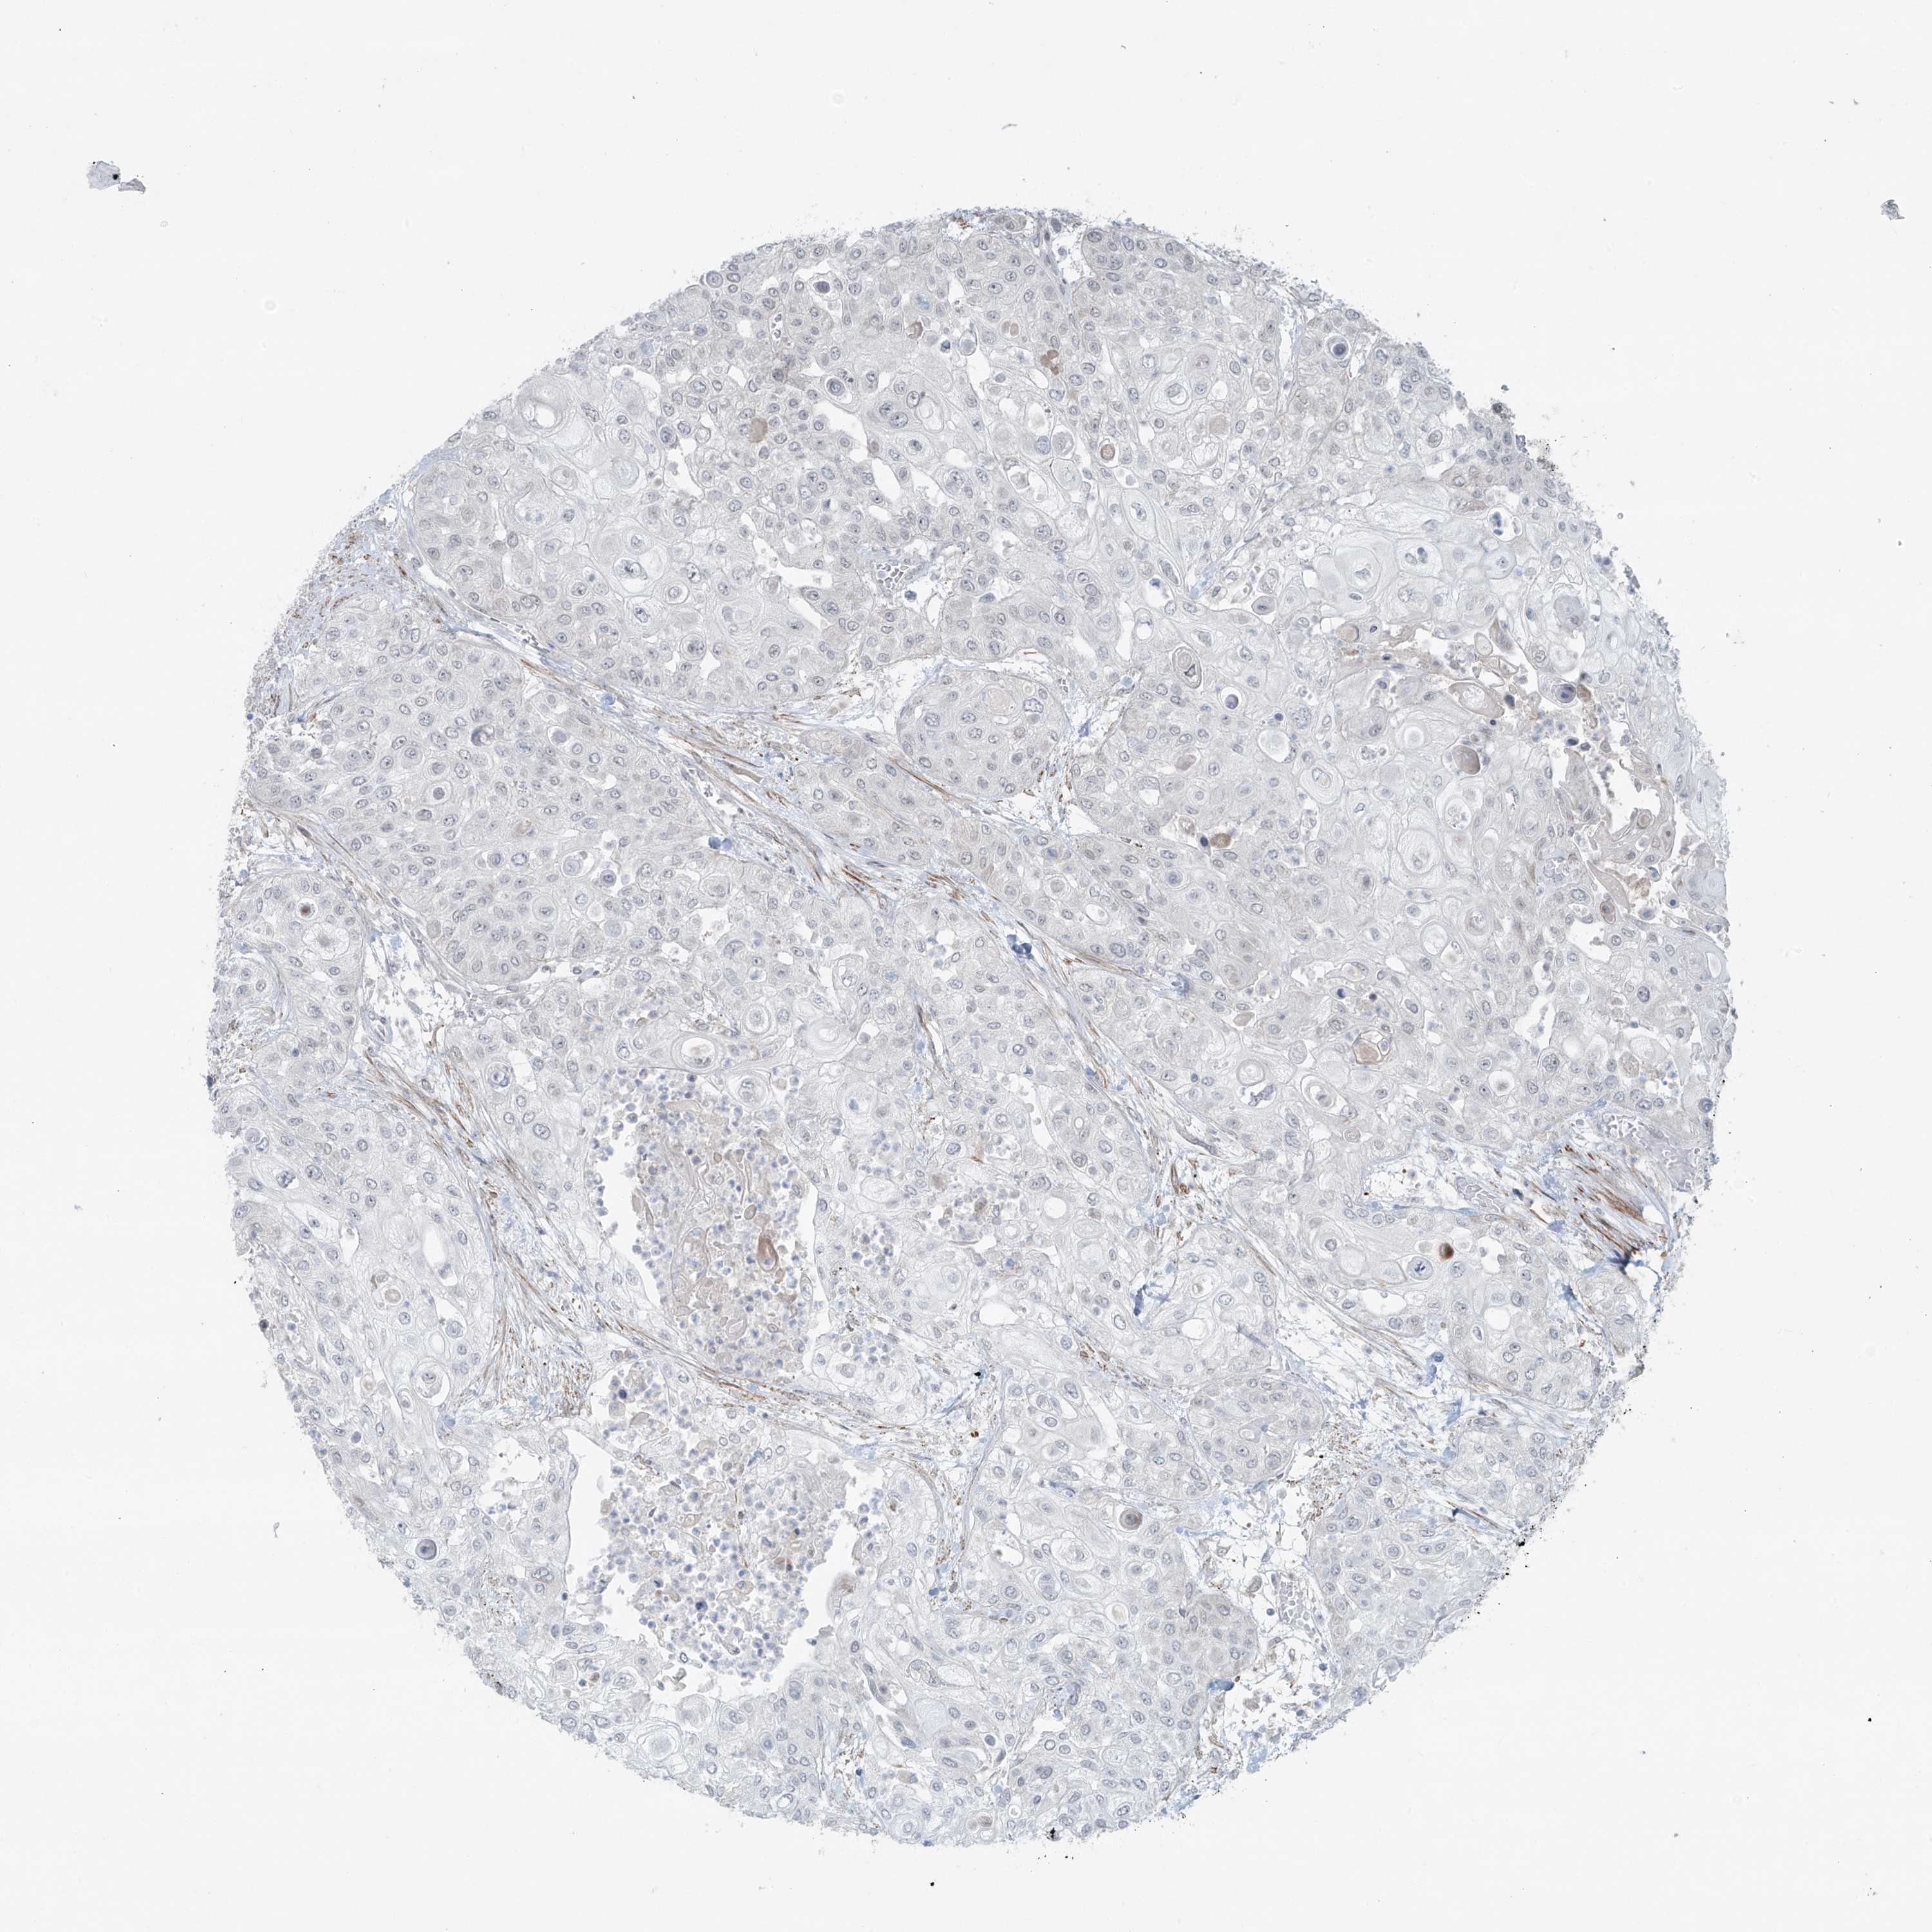

UROTHELIAL CANCER - Protein expressioni

A mouse-over function shows sample information and annotation data. Click on an image to view it in a full screen mode. Samples can be filtered based on level of antibody staining by selecting one or several of the following categories: high, medium, low and not detected. The assay and annotation is described here.

Note that samples used for immunohistochemistry by the Human Protein Atlas do not correspond to samples in the TCGA dataset.

Antibody stainingi

Antibody staining in the annotated cell types in the current human tissue is reported as not detected, low, medium, or high, based on conventional immunohistochemistry profiling in selected tissues. This score is based on the combination of the staining intensity and fraction of stained cells.

Each image is clickable and will lead to virtual microscopy that enables deeper exploration of all samples and also displays staining intensity scores, fraction scores and subcellular localization as well as patient and tissue information for each sample.

Antibody HPA035593

Staining

High

Medium

Low

Not detected

Intensity

Strong

Moderate

Weak

Negative

Quantity

>75%

75%-25%

<25%

None

Location

Nuclear

Cytoplasmic/membranous

Cytoplasmic/membranous,nuclear

Urothelial carcinoma, High grade

Urothelial carcinoma, Low grade